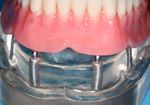

الجراحات التعويضية للتركيبات الغير ثابتة

وفي الأسواق اليوم نماذج كثيرة من الزرعات التيتانية التي أصبحت الشكل الوحيد المقبول للتعويض عن فقدان الأسنان، وهناك تقنيات عدة لتثبيتها منها ما يعتمد على الغرس بطورين من الزمن؛ تبقى الزرعة في الطور الأول مطمورة في العظم ويثبت الجزء البارز من اللثة في الطور الثاني، ومنها ما يأخذ شكله النهائي مباشرة في عمل جراحي واحد. وتثبت الإحصاءات نجاح النمط الأول بنسبة أعلى من النمط الآخر.

تكون الغرسة مفردة أو متعددة أو شاملة، ويميز في طب الأسنان بين أربعة أنواع من الغرسات: التثبيت بالغرسة عبر السن transdental fixation والغرسة تحت الغشاء المخاطي submucosal implant والغرسة تحت السمحاق subperiosteal implant والغرسة في العظم enossal implant.